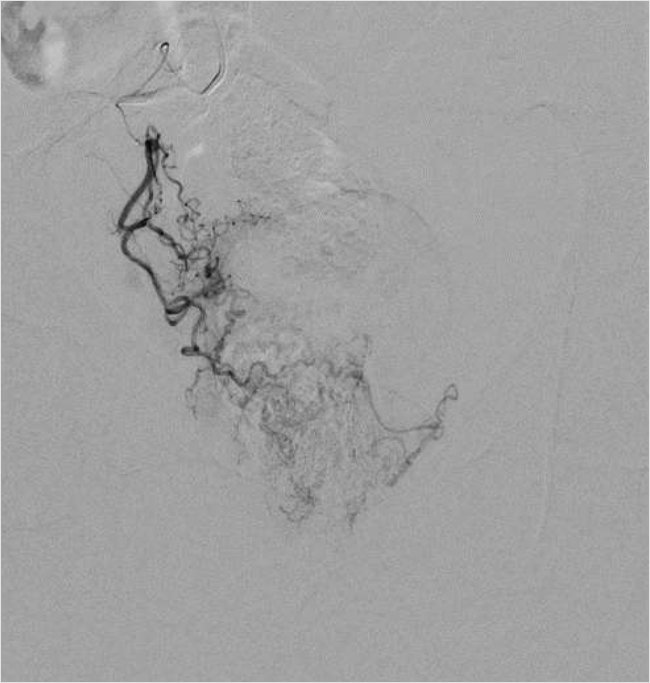

Рисунок 2. Селективная катетеризация простатической артерии справа. Ангиография простатической артерии справа до эмболизации

Для катетеризации простатических артерий по диагностическому проводнику был заменен катетер на диагностический гидрофильный катетер Terumo 4F длиной 150 см и микрокатетер Progreat Lambda 1,9F длиной 175 см с интервенционным гидрофильным проводником 0,014. Микрокатетер избирательно по интервенционному проводнику был поэтапно позиционирован в правой и левой простатической артерии (рис. 3, 5).